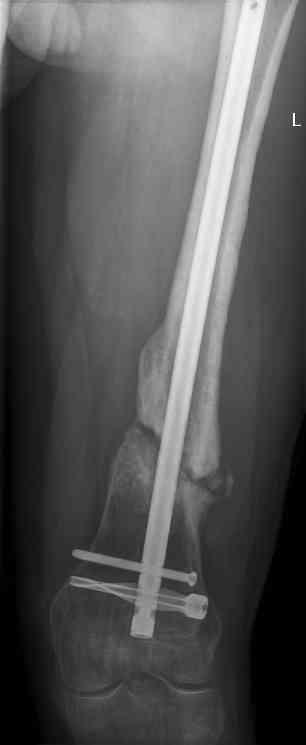

feb 07: retrograde nail + bone graft + BMP

may 07: dynamisation nail

sept 07: locking screw removal (max. dynamisation reached)

nov 07: persistant non-union distal femur; other fractures healed

uneventfully.

All with gradual/partial weightbearing etc. Currently 50-100% weight

bearing, no pain.